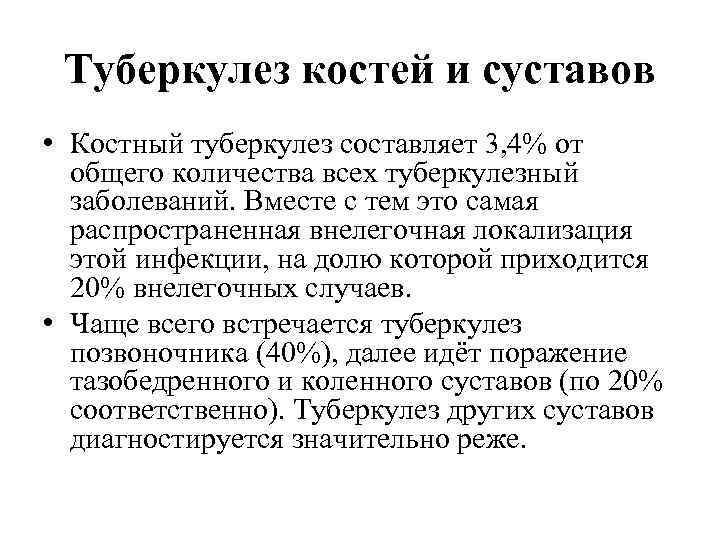

Туберкулез костей и суставов • Костный туберкулез составляет 3, 4% от общего количества всех туберкулезный заболеваний. Вместе с тем это самая распространенная внелегочная локализация этой инфекции, на долю которой приходится 20% внелегочных случаев. • Чаще всего встречается туберкулез позвоночника (40%), далее идёт поражение тазобедренного и коленного суставов (по 20% соответственно). Туберкулез других суставов диагностируется значительно реже.

Туберкулез костей и суставов • Костный туберкулез составляет 3, 4% от общего количества всех туберкулезный заболеваний. Вместе с тем это самая распространенная внелегочная локализация этой инфекции, на долю которой приходится 20% внелегочных случаев. • Чаще всего встречается туберкулез позвоночника (40%), далее идёт поражение тазобедренного и коленного суставов (по 20% соответственно). Туберкулез других суставов диагностируется значительно реже.